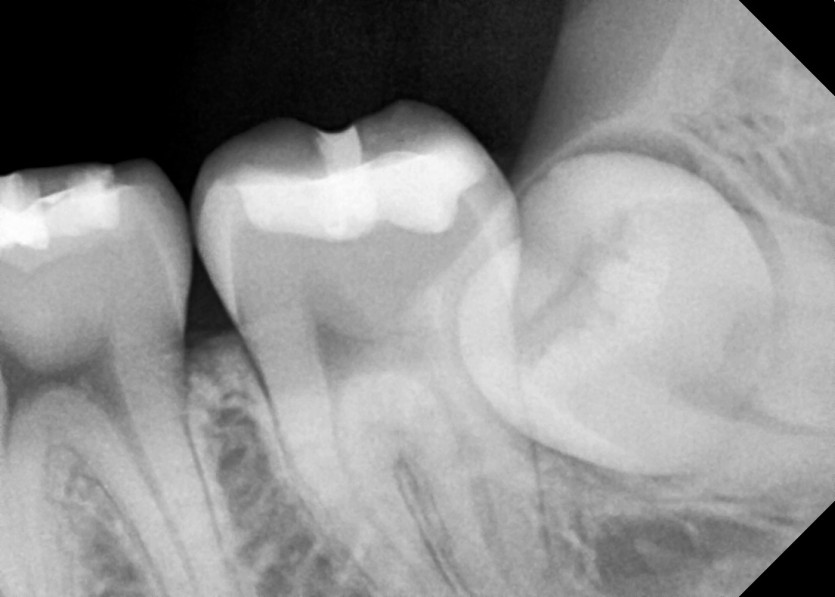

#38,48 사랑니 발치

구강 외과 전문의가 당일 발치했습니다.